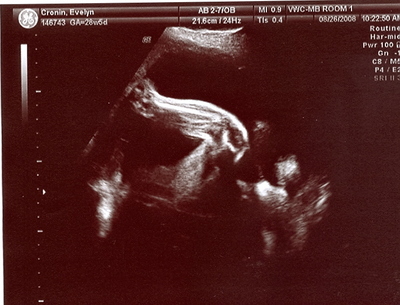

Bean Close up:

There is a right leg (with foot just out of the picture), her right eye, her nose and mouth, AND right to the side of her head (a little above her eye) is her right hand.  She was laying with both hands behind her head and her knees bent and pulled up to her chest.  By her measurements, she is already  weighing in at 3 lbs, 3 oz.